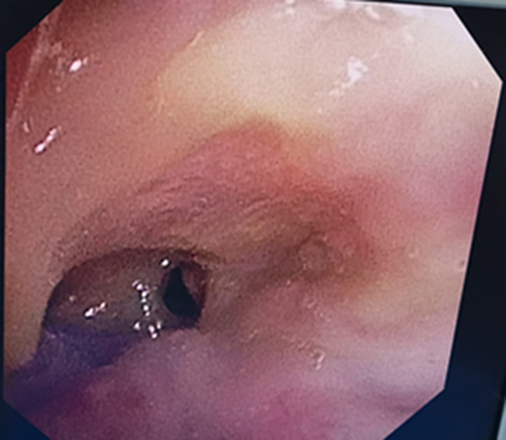

与患者家属充分沟通后,由李乾兵副主任医师主刀,徐裕丰副主任医师、叶鹏、余艳主治医师协助,经喉罩全麻,在支气管镜下运用球囊扩张导管、冷冻治疗仪对狭窄主气管行球囊扩张术及气管增生组织冷冻消融术,操作过程顺利,无明显出血等并发症。术后患者有效通气气道明显增大,气管扩张直径为16mm,呼吸困难症状消失,能够下床活动,生活质量明显改善。

治疗后